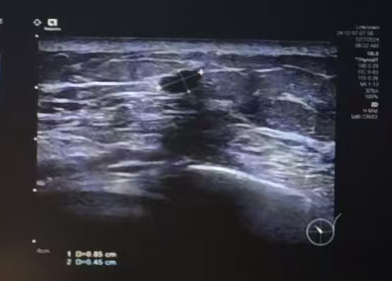

左侧乳腺钼靶(2024年05月22日 我院):

图 左侧乳腺钼靶:(2024年05月22日 我院)

1、左乳多发结节,BI-RADS 3类

2、左侧腋下多发肿大致密淋巴结,建议进一步检查

胸部CT(2024年05月22日 我院):

图 胸部CT(2024年05月22日 我院)

1、右侧乳腺术后改变,术区周围皮肤增厚,考虑复发可能,请结合临床。

2、右侧胸背部肌肉肿胀,肌间隙及皮下多发结节影,右前上纵隔及左侧腋窝多发增大淋巴结影,最大约3.6*2.7cm,左前胸壁皮下多发结节影,最大约1.6*1.1cm。

3、右侧胸膜多发结节状增厚,右侧少量胸水,右肺下叶实性小结节影,考虑转移。

腹部CT、锁骨淋巴结彩超、头颅核磁、全身骨扫描未见明显全身转移征象。